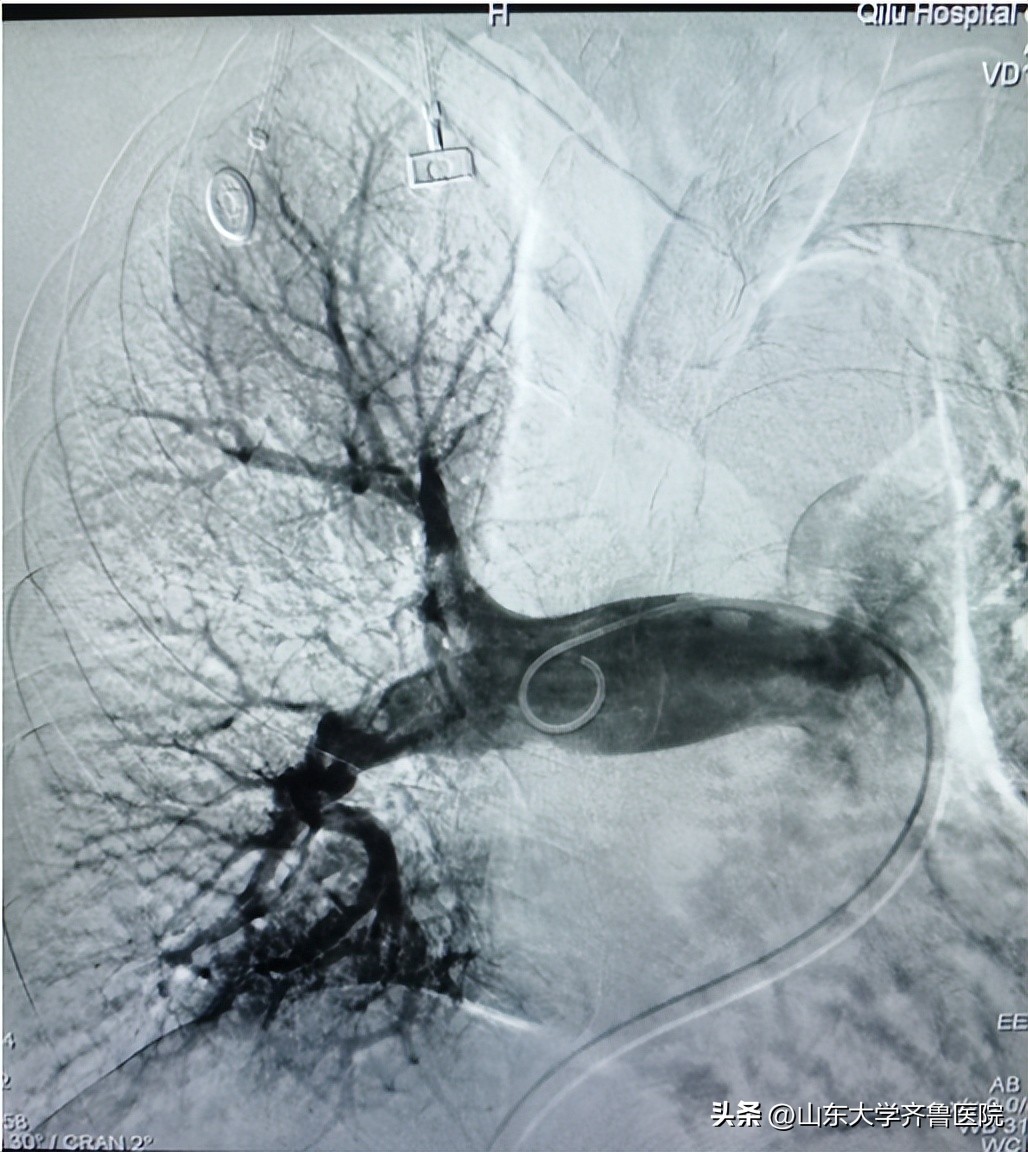

手术将血栓抽吸导管沿导丝推送至右肺动脉干后进行抽吸,抽出大量条状及块状红色血栓;再将肺动脉取栓系统在残余栓块中释放网盘支架,吸附残余栓子后回收至抽吸导管;造影见右肺动脉血栓清除率约70%,血流通畅PFG3级,术后测肺动脉压力明显下降。经血管造影确认血栓清除达到目标后结束手术。国产SIRIUS TWIFLOW®肺动脉取栓系统与血栓抽吸导管的联合治疗急性肺栓塞具有显著的临床效果,同时操作简单、手术时间短、安全性高等特点。